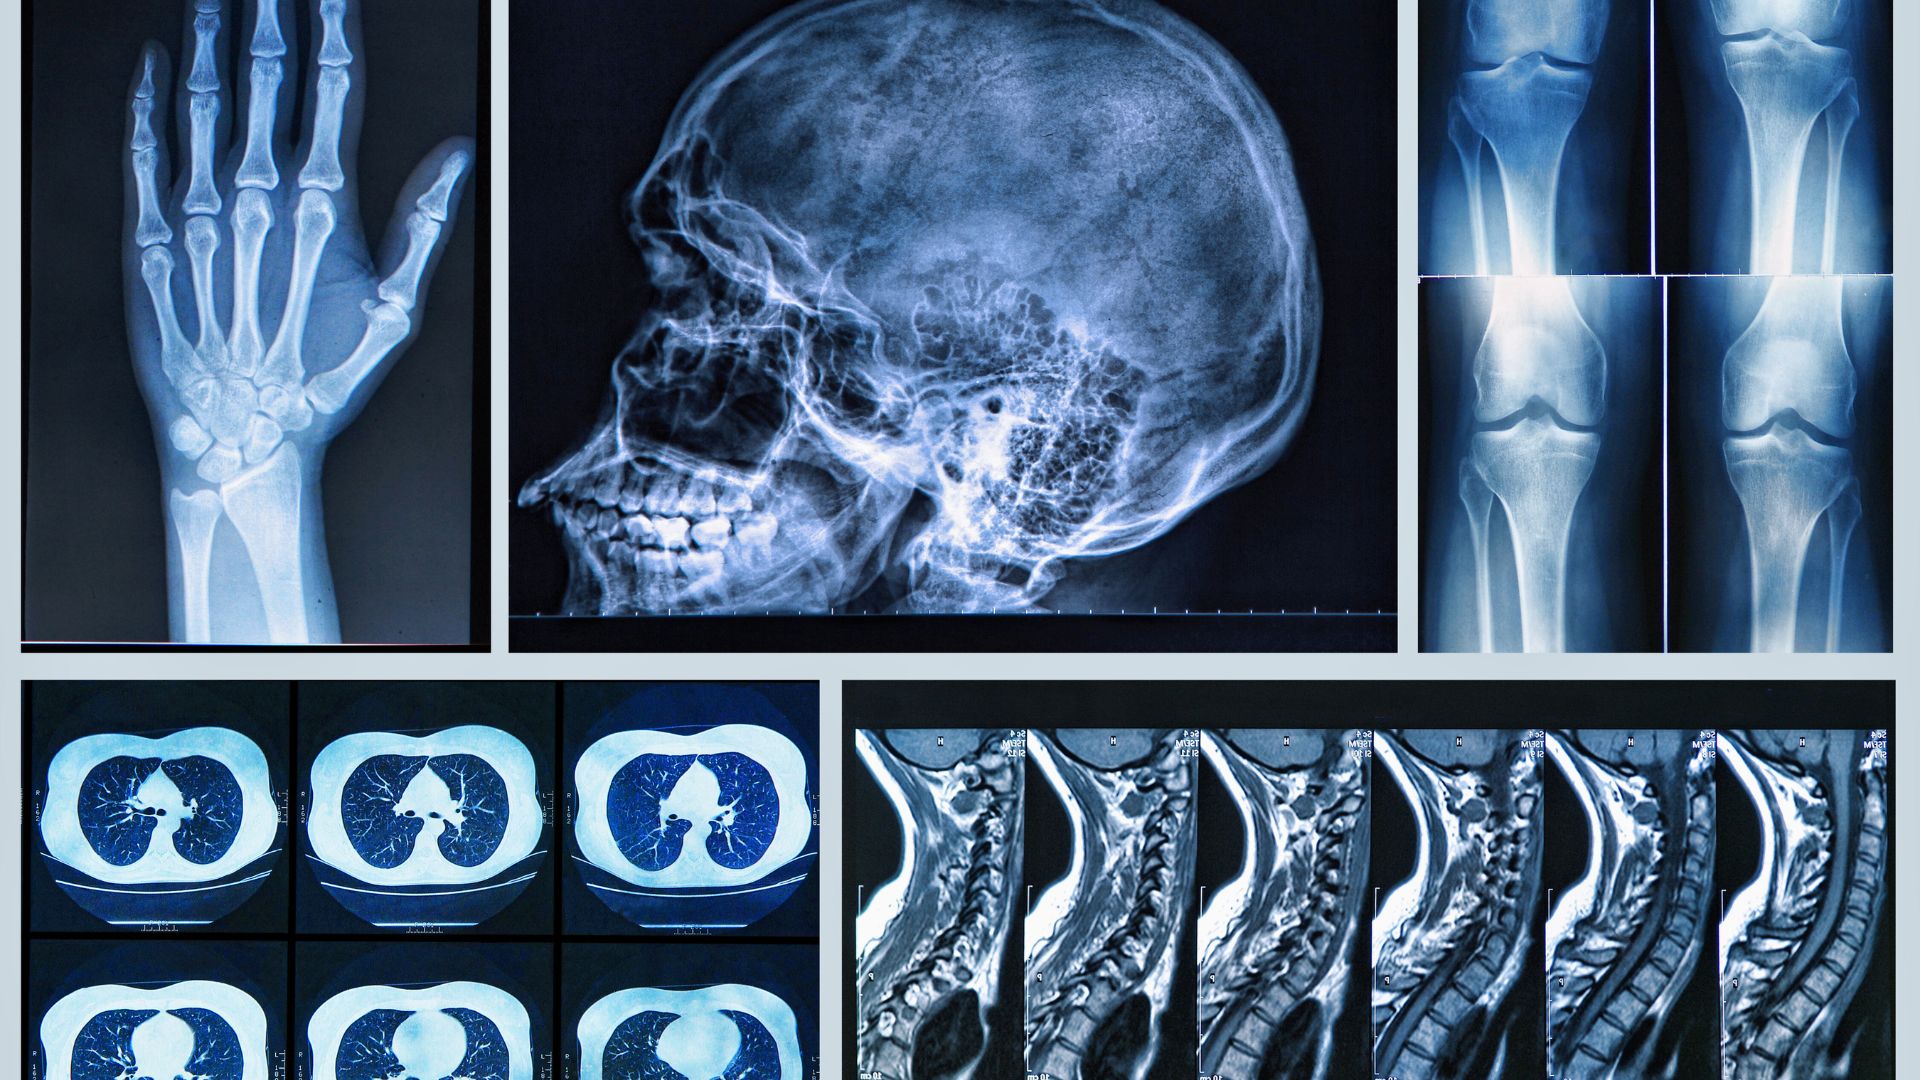

Prise en charge des fractures, entorses, arthroses et pathologies ostéo-articulaires.